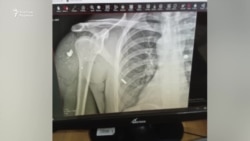

Алматы облысында тұратын Руслан Кемелбаев қаңтар оқиғасы кезінде жараланған. Иығына оқ тиіп, ондаған бытыра көкірек тұсына шашылып кеткен. Кемелбаев "репрессиядан қауіптеніп, жараланғанымды ашық айтпадым" дейді. Бірақ полиция өткен аптада оның үстінен іс қозғалғанын хабарлаған.